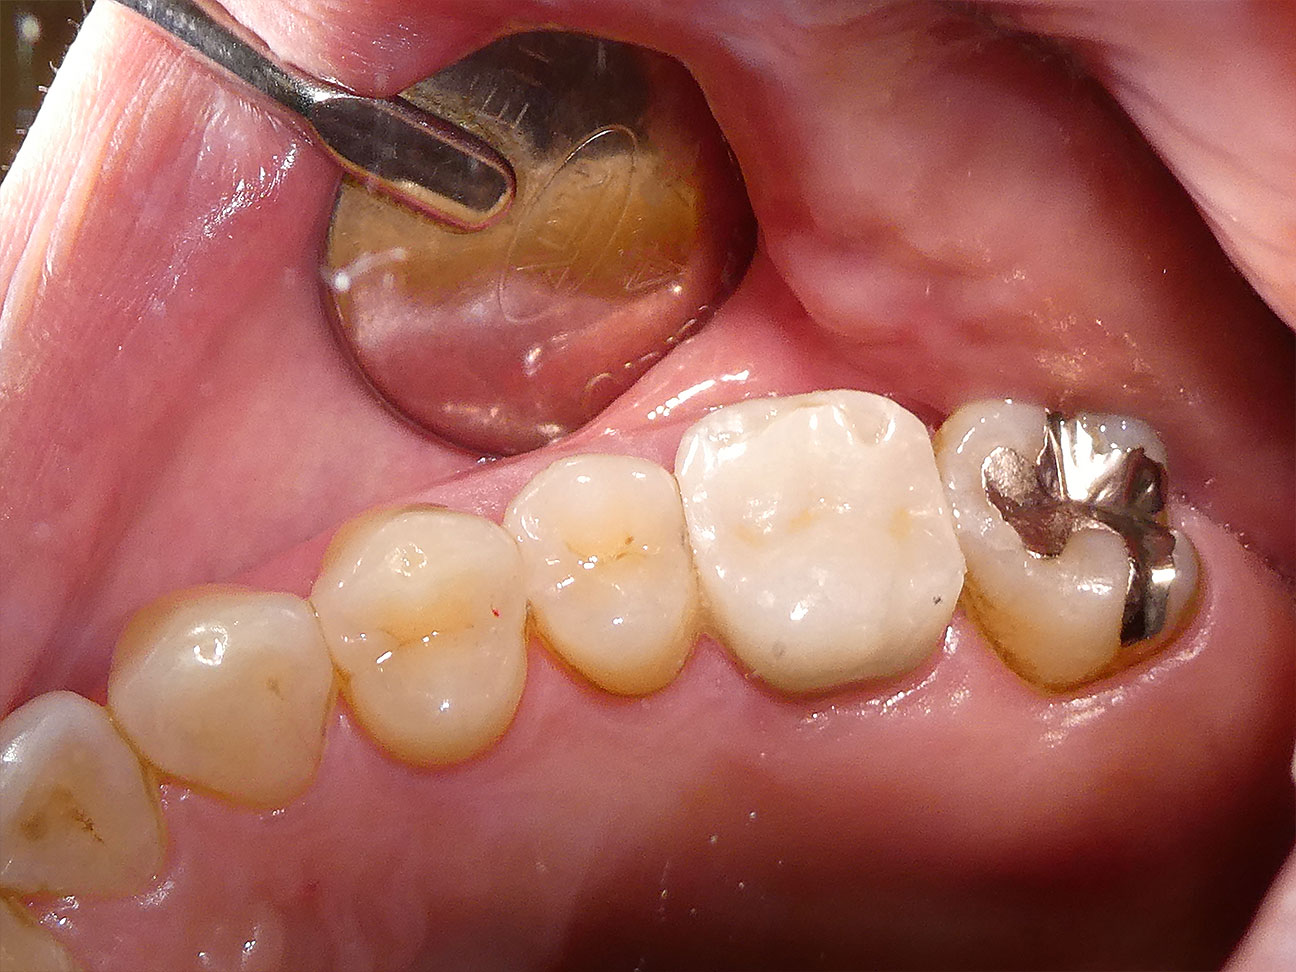

STEP6 完成したジルコニアアンレー

印象から約10日で完成したジルコニアアンレーをお口に接着し治療を終えました。このように自然な白さで審美性も高く、ご自分の歯との隙間もなくピッタリと接着されていることがお分かり頂けると思います。やみくもに自費の治療をお薦めするような事は、大塚歯科クリニックでは致しません。天然歯(ご自分の歯)を最大限大切に残すことを第一にリスクと費用をお伝えしながら、患者さんのご希望とお考えを考慮して機能性と審美性にご満足頂ける治療を選択しました。定期検診を通して今後も患者さんを見守って参ります。